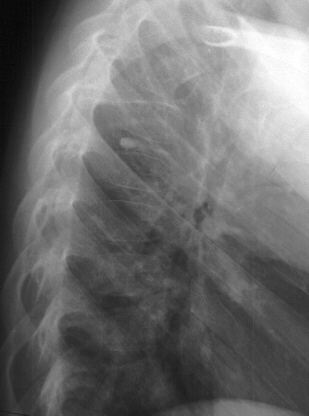

Patient is a 4 year old male who developed the insidious onset of neck pain and stiffness 4 days prior to admission. Over the intervening period, the patient suffered from worsening of his symptoms which led to increasing irritability and difficulty sleeping. On the day of admission, he was seen by a local pediatrician for severe neck pain. It was observed that his head was in a fixed position just slightly right of midline. The patient's past medical history was remarkable for two recent self-limited episodes of hives and urticaria on his trunk and extremities that was treated with prednisone. There was vague history of remote trauma about one month previously when the patient had been "horsing" around with his brother. The child had no evidence of a viral prodrome, constitutional symptoms or travel history. He was sent to a local hospital where radiographs of the cervical spine demonstrated calcifications in the C3-4 and C5-6 intervertebral disc spaces . Neurological exam was normal. The child's pain was refractory to morphine treatment and he was transferred to A.I. for the management of his intractable pain. On arrival, his physical exam was unchanged. Blood work revealed a WBC count of 12.7K with 75% PMNs and an ESR of 80. Radiographs of spine showed the presence of an addition calcification in his thoracic spine . He was treated with oral valium and a soft cervical collar. Over the ensuing 24 hrs the child demonstrated marked improvement of his symptoms and was switched to motrin. He was subsequently discharged.

The number of calcified discs varied from 1 to 12 (mean 1.69) . Symptomatic calcified discs are most common at C6-7. Radiologic examination shows images of calcium density in the normally radiolucent intervertebral discs. Anterior or posterior protrusion can be observed. The lesions demonstrate high density on CT and low signal intensity on MRI.